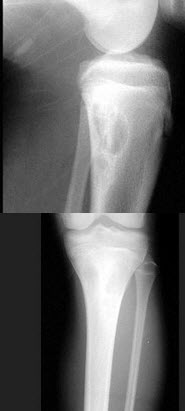

15、单项选择题

女,27岁,有外伤史,结合图像,最可能的诊断是()

A.骨斑点症

B.骨梗死

C.骨岛

D.皮肤骨膜肥厚症

E.石骨症